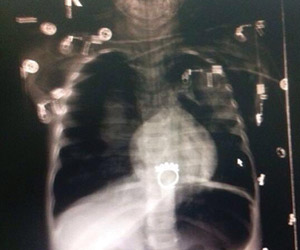

وكتب الطبيب المعالج في تقريره الذي حصلت "الوطن" على نسخة منه: أن "الطفلة سولاف" البالغة من العمر ثلاث سنوات أدخلت إلى المستشفى يوم الأربعاء الموافق 24 / 6 / 1436 هـ، بعد أن ابتلعت جسما غريبا، وعلى الفور أخضعت للفحوصات اللازمة، وتم عمل منظار علوي للمريء تحت مخدر عام، حيث أظهر وجود خاتم معدني وبه ثلاث وردات موجوداً أسفل العضلة العاصرة بأعلى المريء مباشرة، وحاولت إزالته بسن الفأرة ولكن لم أستطع، ثم سقط الجسم الغريب إلى القاع، وحاولت إزالته مرة أخرى لكنه التصق بالمريء، ثم تدهور وضع الطفلة، وتوقف التنفس، ثم حدث لها توقف قلبي رئوي، وتم عمل انعاش قلبي رئوي لها بواسطة طبيب التخدير، فأفاقت، ثم تم عمل أشعة عادية على الصدر أظهرت وجود استرواح هوائي بجانبي الصدر، مع احتمال كبير لتهتك المريء".

وأضاف "باستشارة جراح القلب والصدر قام بتركيب أنبوب بجانبي الصدر، وكذلك باستشارة جراح الأطفال أجرى استكشافا جراحيا لإزالة الجسم الغريب، ثم ركب للطفلة أنبوبا أنفيا، ونصح باستمرار العلاج التحفظي ثم نُقلت المريضة إلى العناية المركزة، وأظهر الفحص أن درجة الحرارة 39 والضغط 115/57 ومعدل النبض 200 والبطن منتفخ قليلاً، والصدر مثبت به أنبوب بالجانبين مع وجود تسرع بضربات القلب، واستجابة قليلة لحدقة العينين، وكانت نتيجة الفحوصات المخبرية طبيعية، ثم بدأت المريضة تتنفس بصعوبة على جهاز التنفس الصناعي، ثم عانت من توقف قلبي وتم عمل إنعاش قلبي رئوي لها، ولكنها توفت إلى رحمة الله تعالى في تمام الساعة 2:48 فجر الخميس الموافق 25/2/1436هـ وشُخصت حالتها على أنها اشتباه ثقب بالمريء وتوقف قلبي أثناء عمل منظار لإزالة جسم غريب بالثلث العلوي بالمريء".